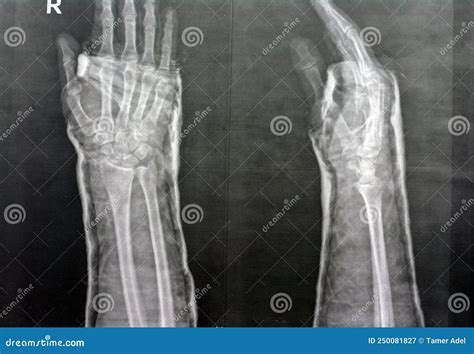

An MRI wrist joint scan is a non-invasive imaging technique that uses magnetic fields and radio waves to produce detailed images of the wrist. Unlike X-rays, which primarily show bones, MRI scans can visualize soft tissues such as ligaments, tendons, and cartilage. This makes MRI particularly useful for diagnosing conditions that affect these structures, such as fractures, ligament tears, and arthritis.

• Fractures: MRI can detect fractures that may not be visible on X-rays, especially in the early stages.

• X-Rays: Useful for detecting bone fractures and certain types of arthritis.

• CT Scans: Provide detailed images of bones and can be useful for detecting fractures and bone abnormalities.